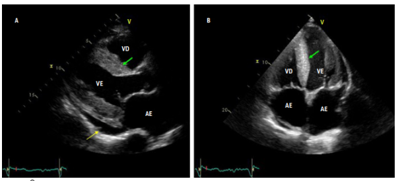

Ecocardiograma: fração de ejeção do ventrículo esquerdo: 52%

Imagem 1

Imagem 2: